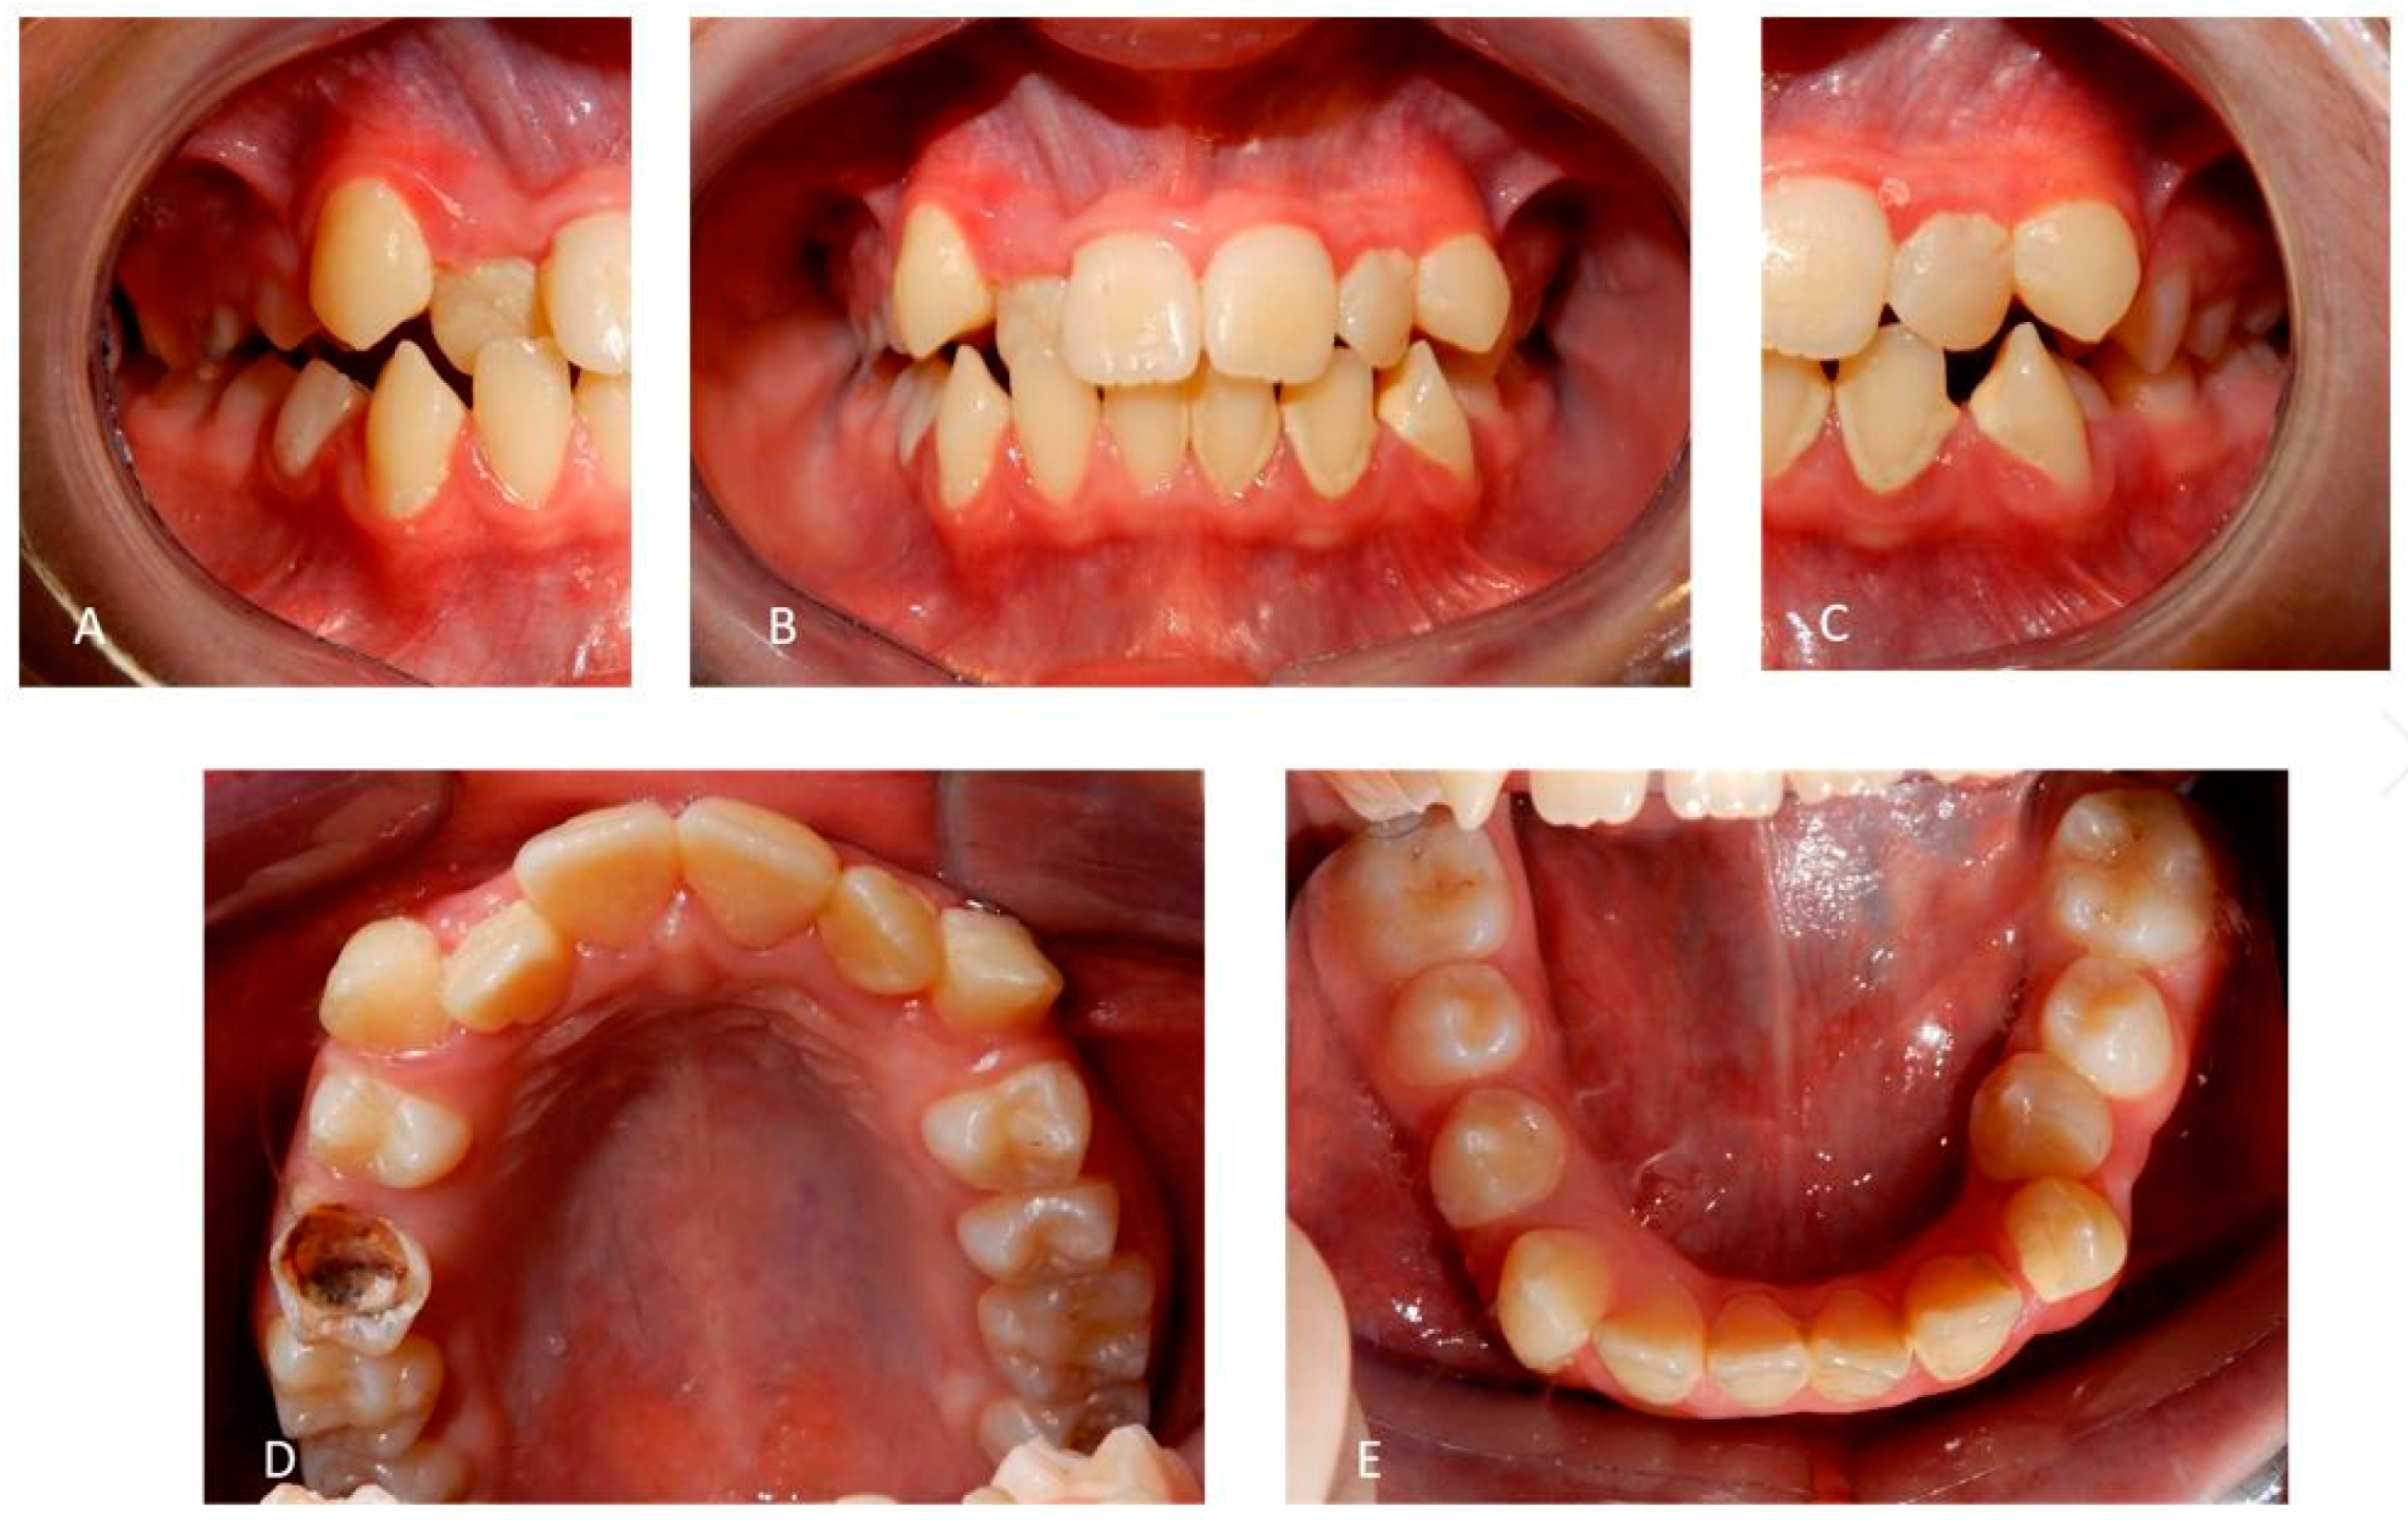

2.1. Patient A

2.2. Patient B